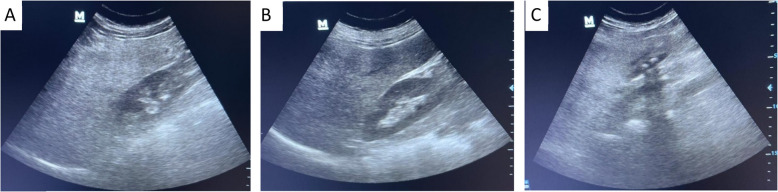

Results: MAFLD prevalence was 46.33%. FIB-4 with an AUC of 0.826 (95% CI:0.778-0.875)and NFS with an AUC of 0.964 (95% CI:0.942-0.986) demonstrated high diagnostic accuracy for fibrosis, while HSI with an AUC of 0.847 (95% CI:0.803-0.890) and FLI with an AUC of 0.835 (95% CI:0.789-0.881) effectively identified hepatic steatosis. The HSI (38.31 ± 6.93) and FLI (68.78 ± 29.98) placed patients in the high probability category for liver steatosis, while the FIB-4 (1.94 ± 0.81) and NFS (0.56 ± 1.24) scores indicated moderate fibrosis risk. Ultrasound findings corroborated these results, with 80.58% of patients presenting with mild to moderate steatosis. Higher BMI, increased waist circumference, elevated liver function markers (elevated ALT, AST, GGT, and albumin), higher lipid profile, and poor glycemic control (HbA1c) were key predictors of MAFLD.